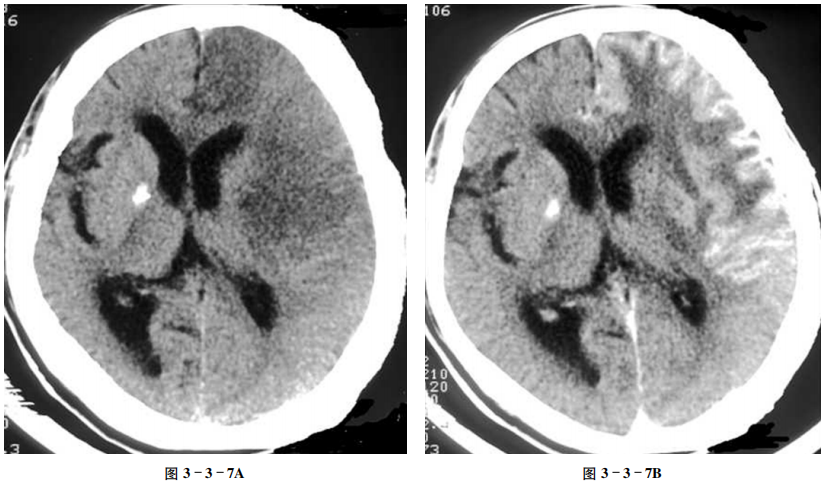

大脑半球脑梗死(亚急性期)

【病史摘要】

男性,69岁。突然肢体乏力、跌倒伴言语不清,脑梗死治疗后15天。

【CT表现】

平扫示左侧额、颞叶大片状低密度区,局部脑沟及左侧大脑外侧裂池消失,左侧脑室前角较右侧稍窄(图3-3-7A);增强扫描示病变脑回状强化(图3-3-7B)。

【重要征象】

脑血管分布区大片状低密度,脑回样强化。

【CT拟诊】

①脑梗死。②病毒性脑炎。③脑膜脑炎。④脑肿瘤。

【最终诊断】

大脑半球脑梗死(亚急性期)。

【评述】

在脑梗死早期,尽管梗死区血脑屏障被破坏,血管通透性增加,但因侧支循环尚不充分,CT增强扫描通常不易发生强化。一般在梗死后5~6天出现强化,2~3周后发生率最高,强化也最明显,可持续到第8周。一般认为是与梗死后血脑屏障被破坏、新生毛细血管增生,同时伴侧支循环形成、局部大量血流过度灌注有关。

CT表现

(1)CT平扫病变区为低密度,其不同时期的特点及伴随征象见本节例6。(2)增强扫描80%~93%梗死区可发生强化,多出现在脑皮质及基底核,可表现为:①脑回状强化最常见。②点线状强化。③团块状强化。④环状强化。前两种强化均为灰质强化,后两种强化出现在病变中心,团块状强化的形态可与灰质团块形态一致,环状强化最常见于基底核梗死灶的周围。

鉴别诊断

①脑肿瘤:皮层肿瘤多表现为脑回肿胀,灰白质分界不清,具有占位效应,低级别胶质瘤一般无强化,高级别胶质瘤以花环状强化为主。本例以脑回样强化,在脑肿瘤中相对少见。②脑膜脑炎:CT平扫对直接征象敏感性较低,增强扫描可见大脑半球硬脑膜或柔脑膜呈线样强化。临床症状重,多表现为高热、脑膜刺激、颅内高压等。本例临床症状不支持脑炎。③病毒性脑炎:多位于边缘系统,颞叶、岛叶,增强可出现脑回样强化,但患者多有病毒前驱史,临床多伴有发热等症状。